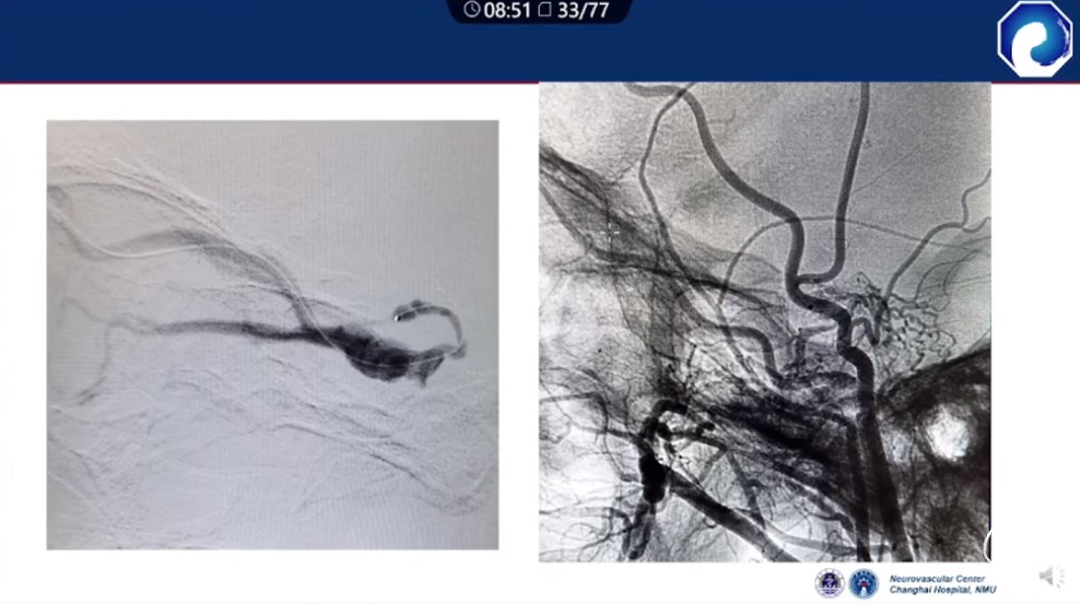

痿口静脉端的识别至关重要。

痿口静脉端精准完全闭塞是DAVF治愈的关键。